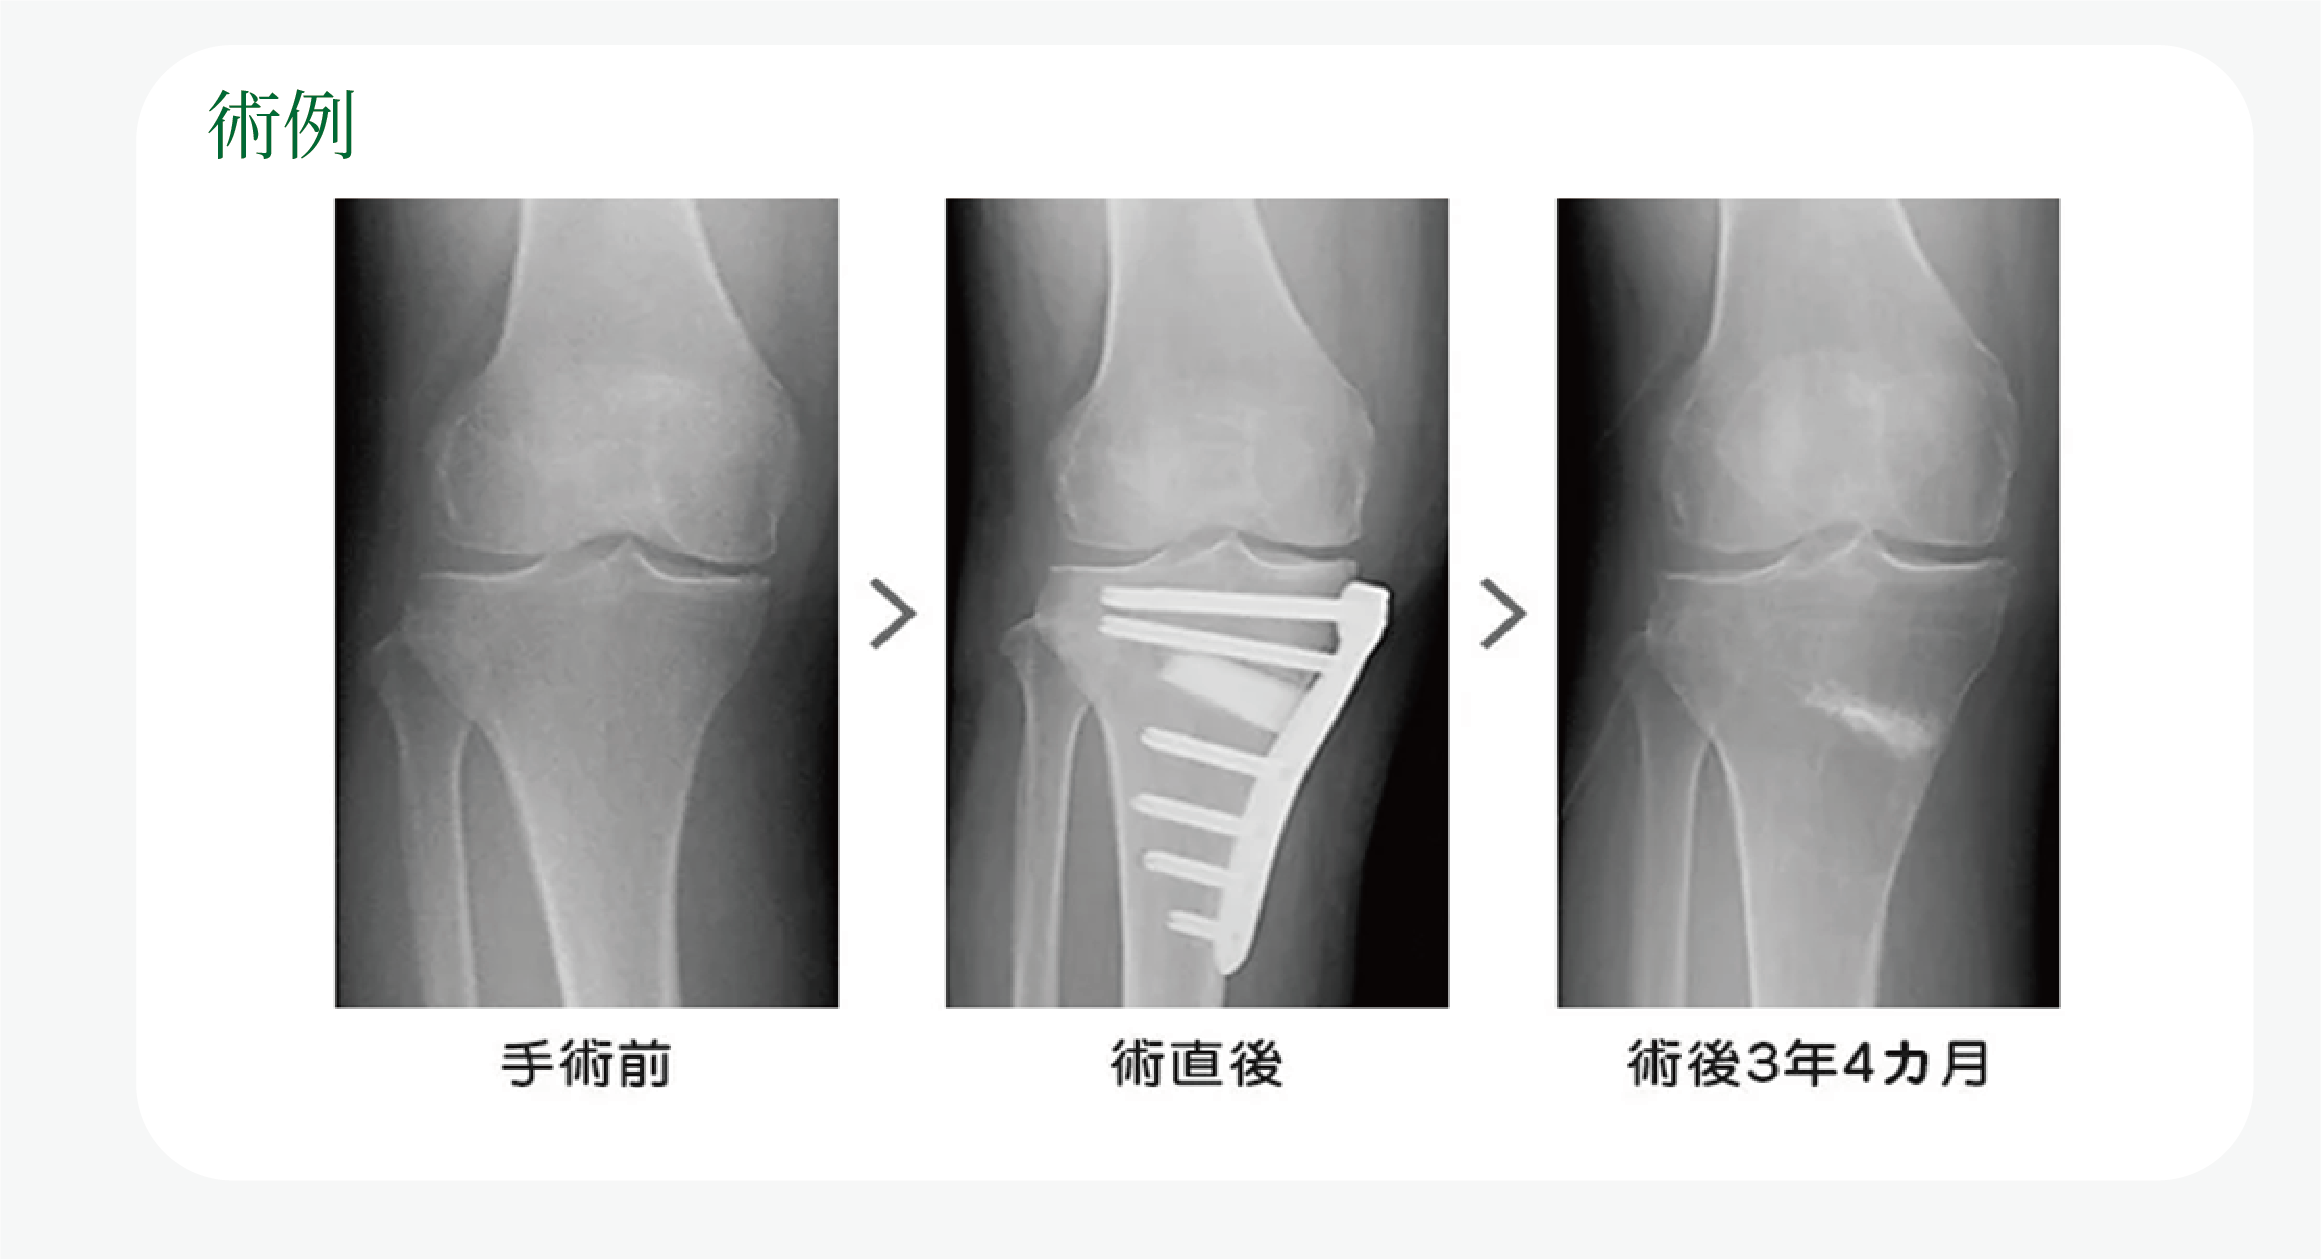

変形性膝関節症とは